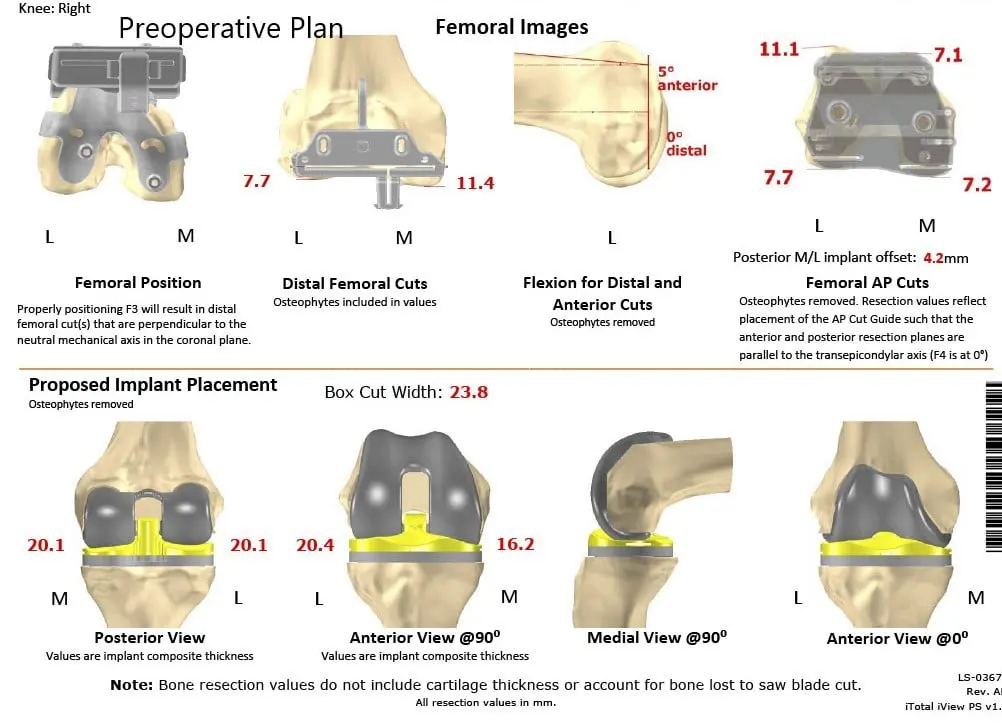

A preoperative CT scan of the right knee with the hip and ankle was taken several weeks prior to the procedure. This aided in a better understanding of the patient’s knee anatomy and biomechanics. The data was used to construct a patient-specific implant. Disposable cutting blocks were constructed for creating bone resection as outlined in a preoperative surgical plan.

Complete Orthopedics patient-specific surgical plan for a customized total knee replacement in a 58-year-old female with arthritis.

Complete Orthopedics patient-specific surgical plan for a customized total knee replacement in a 58-year-old female with arthritis (scan 2)

A preoperative surgical plan outlining the bone cuts and femoral offsets